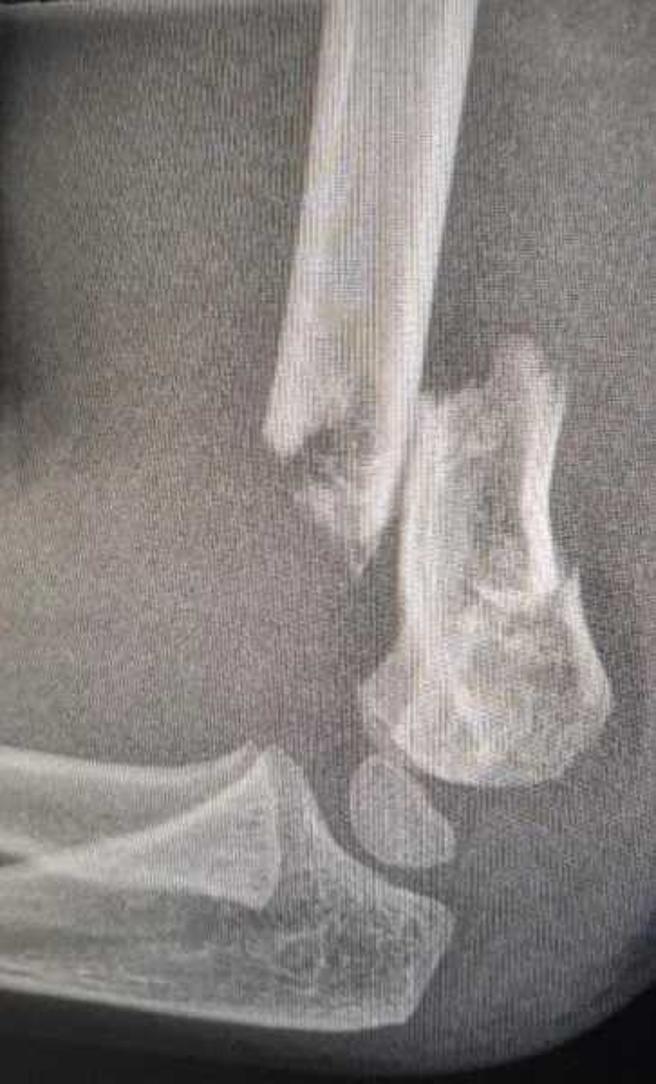

原本以为只是脱臼,但照了X光后,医生表示情况严重,因为骨头断裂后,有部分骨头往后移,假如伤及神经,左手可能会有瘫痪的风险,因此只能进行小手术,在手背上固定3个钢钉,让骨头慢慢復位,「但医生也说,儿子的骨头日后会永久性长歪,具体对他的生活会造成什么影响还不能确定」。